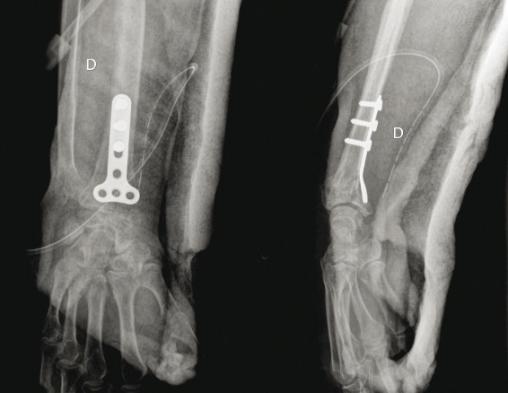

© Henry Coudane, Frédéric Éloy (La Revue du Praticien) (À gauche) Radio de face. (À droite) Radio de profil.